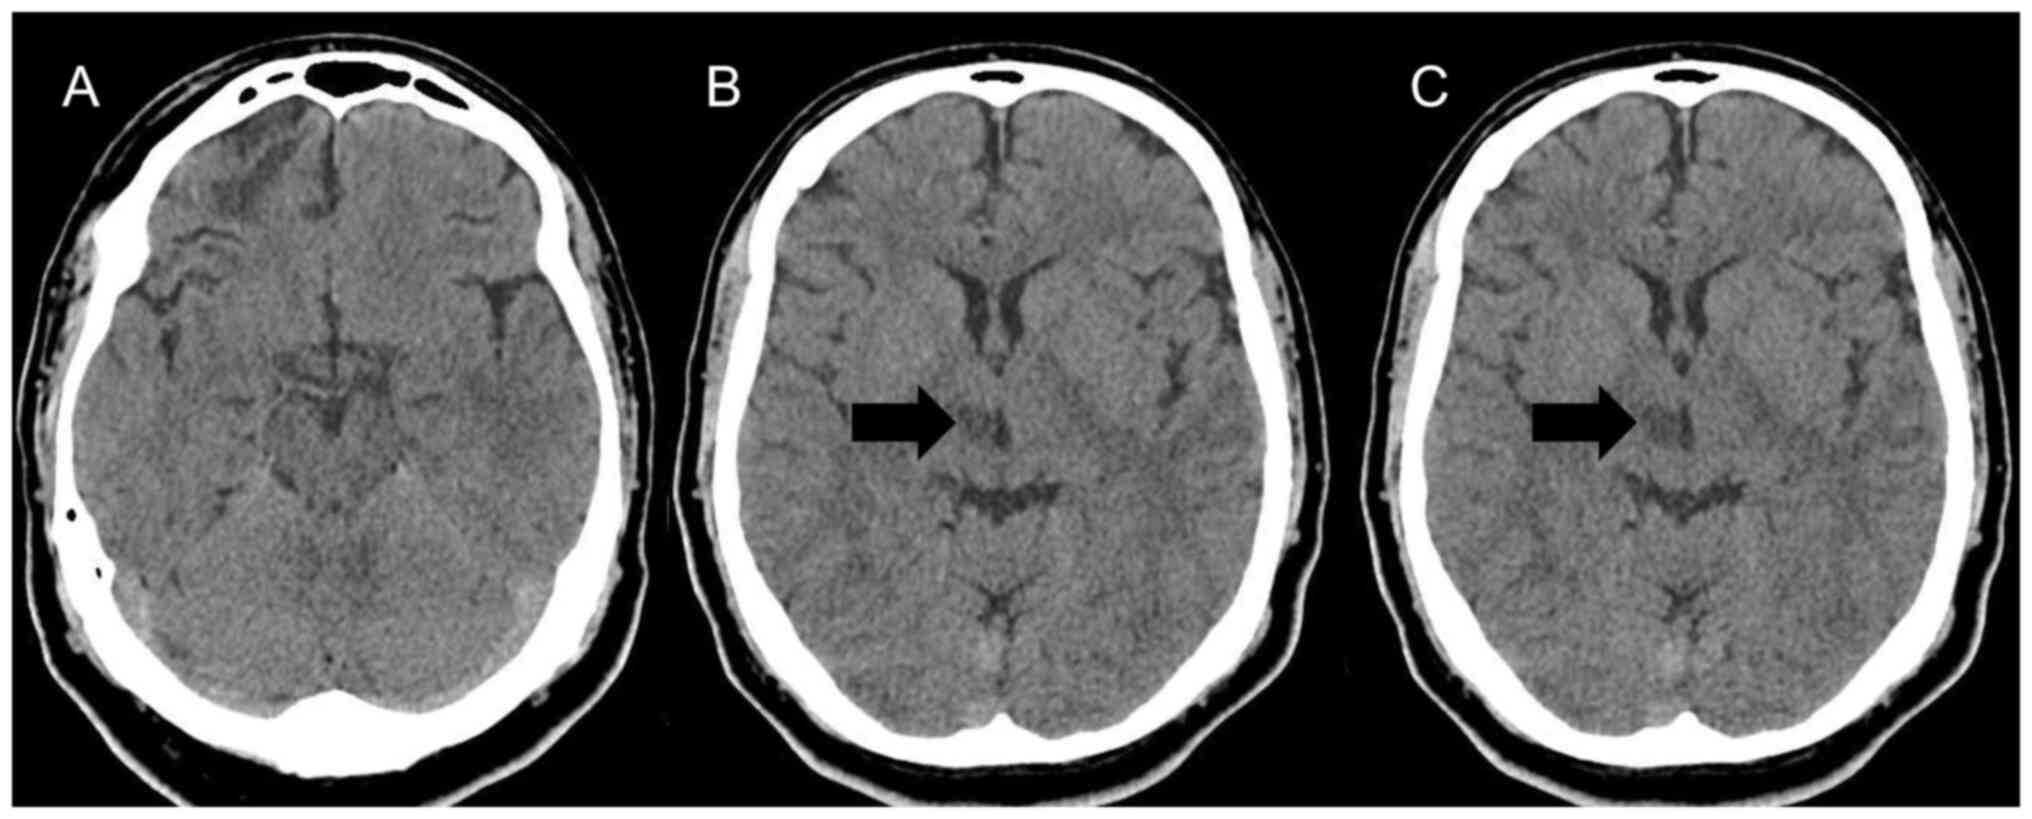

Laboratory tests, including a complete blood count, platelet count, prothrombin time, partial thromboplastin time, serum lipids and inflammatory test results were within normal limits; an investigation for hypercoagulable disorders yielded negative results. A cranial computed tomography (CT) scan revealed a right thalamic infarction (Fig. 1). A brain magnetic resonance imaging (MRI) demonstrated a lesion of 1.2x1 cm in size (data not shown; image not available), limited to the thalamus, which was hyperintense on T2-weighted and fluid-attenuated inversion recovery, consistent with acute ischemic infarct without affecting the subthalamic or midbrain area. Cerebrospinal fluid analysis and culture yielded normal findings.

Figure 1

Neuroimaging illustrating thalamic infarction (arrow). (A) Level of the lower midbrain, (B) level of the upper midbrain, and (C) level of the lower basal ganglia images of an axial cranial computed tomography scan.